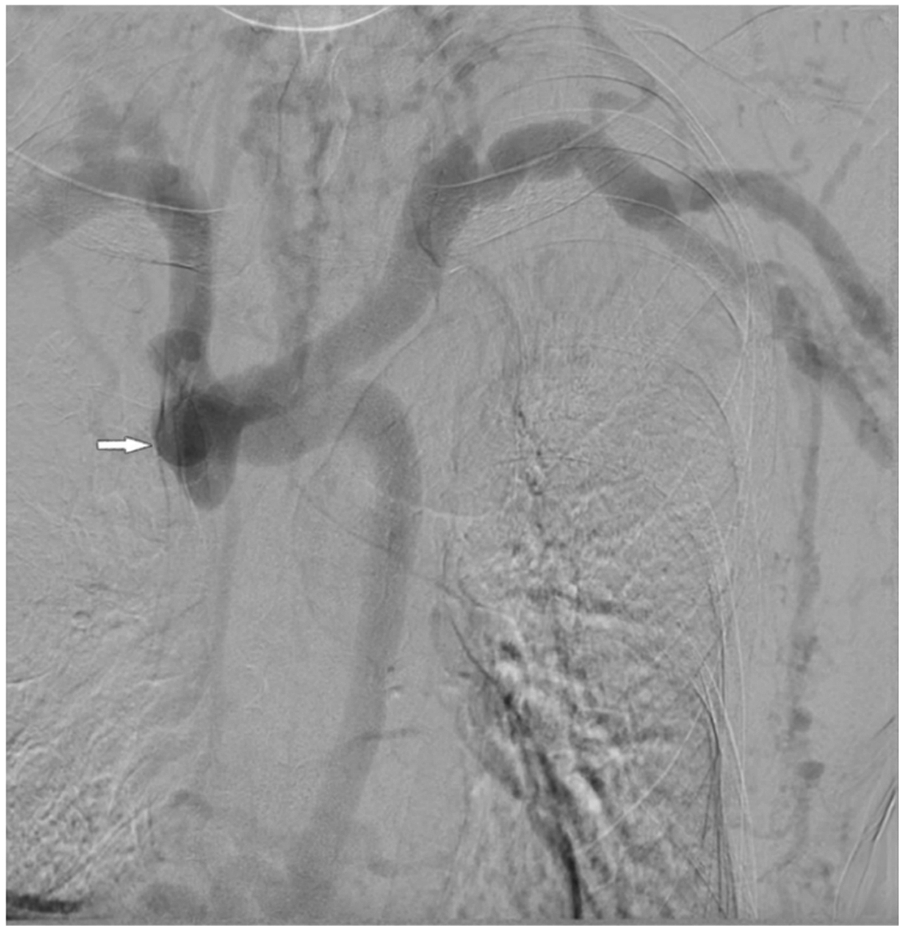

At presentation, vital signs were within normal limits, and there was no swelling or pain in the extremities, neck, or head. Cutaneous examination revealed no congestion or ulceration, infection, nonhealing wounds, or incisions. He also reported no symptoms of the respiratory (hoarse voice, dyspnea) or neurological (visual or auditory disturbances, cognitive disabilities) systems. Blood cell count and liver function were normal. Abdomen ultrasound did not identify cirrhosis, splenomegaly, or portal vein thrombosis. Thoracic computed tomography showed no abnormalities of lung or mediastinum and no pleural effusion. Echocardiography showed no abnormal cardiac structure or function. DSA revealed a complete occlusion of the SVC (Figure 2) and a markedly dilated azygos vein. Vascular access function was further assessed, and color Doppler ultrasound of the AVF identified no fistula stenosis. During multiple dialysis sessions, no increased venous pressure was observed, and there was no prolonged hemostasis after HD. Dialysis adequacy was measured by single pool Kt/V(SpKt/V). The calculated SpKt/V was >1.2. Based on these observations, the patient was determined to have a complete SVC occlusion with markedly dilated thoracoabdominal wall and superficial epigastric veins, but no other venous hypertension symptoms and signs, and no evidence of access dysfunction. After thoroughly discussing the treatment options and associated risks with the patient, a conservative management approach was opted without immediate intervention, but following him closely. Every month, we recorded the appearance, diameter, and size of the lateral branches. We carefully examined whether the patient developed any new related symptoms and signs of SVC occlusion. Every three months, SpKt/V was used to evaluate HD adequacy, and the AVF was monitored by ultrasound.

Figure 2

DSA revealed a complete occlusion of the SVC.